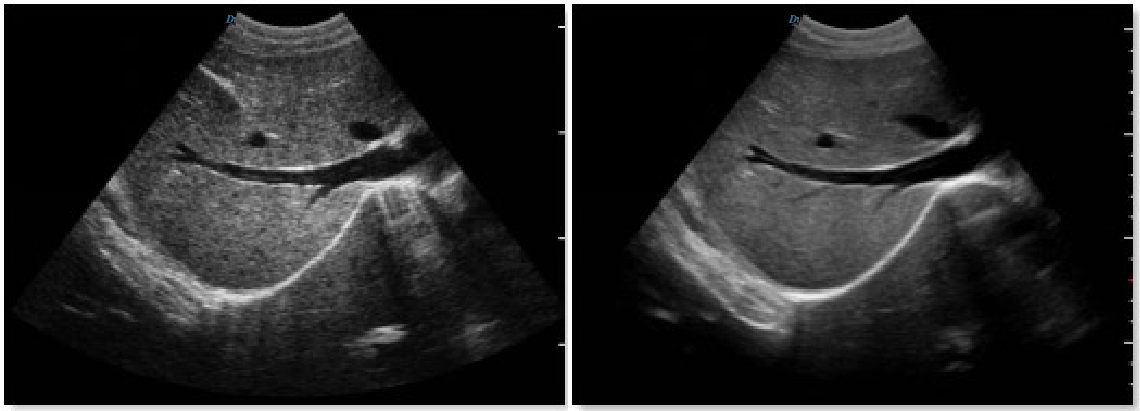

Micron Imaging Technology

Micron imaging technology, real-time tracking of specific signals at the edges of different tissues, to achieve edge enhancement,

and monitor each pixel at the same time; optimize the internal signal of the organization and perfectly integrate the edge

information and the internal pixel information of the organization to restore the real and delicate, excellent level contrast

Two-dimensional image.

Harmonic Imaging Technology(THI)

It improves image clarity by improving tissue contrast resolution, spatial resolution, and eliminating near-field artifacts.

It is mainly used for the diagnosis of cardiovascular and abdominal diseases. It plays an important role in evaluating the lesion area and boundary division of patients with imaging difficulties. The technology has been fully approved by clinicians.

Harmonic technology retains the second harmonic signal to the greatest extent on the basis of removing the fundamental signal, which increases the signal strength by more than 30% compared with the traditional signal processing, reduces noise and artifacts, and improves the contrast resolution of

tissue images.

Trapezoid Imaging

Trapezoid imaging is a kind of expanded imaging, which is transformed into a trapezoid on the basis of the original rectangle, and

the left and right sides are expanded to a certain extent, achieving a wider field of view. The principle of ultrasound imaging is

to scan the human body with ultrasonic sound beams, and obtain images of internal organs by receiving and processing the reflected

signals.